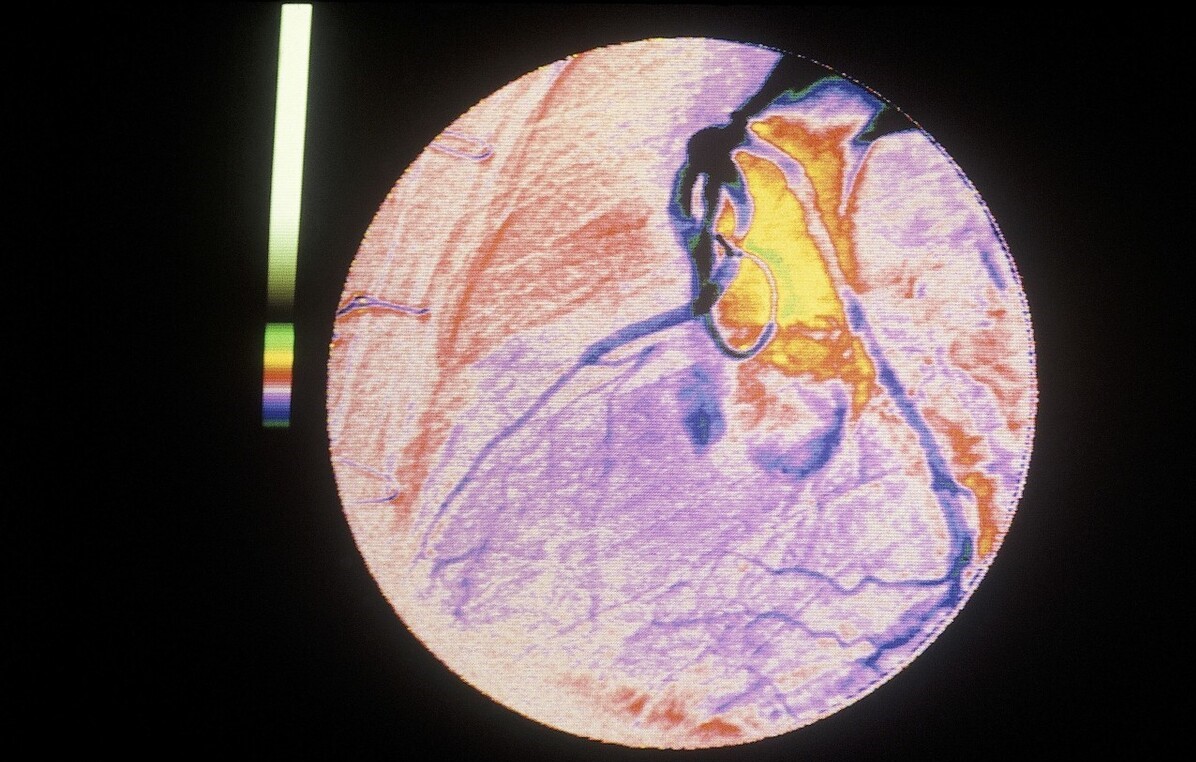

所以说,虽然心电图可以提示“心肌缺血”,但仅靠心电图并不能诊断冠心病。一般来说,只有当冠状动脉狭窄程度超过50%的时候,才会确诊为冠心病。对冠脉狭窄程度的判断,需要进行冠脉造影才能明确,这也是诊断冠心病的“金标准”。